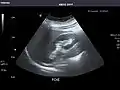

- Left kidney

Kidneys: Right and left kidneys measure 11.5 cm and 12 cm in length respectively. No hydronephrosis. Small left lower pole kidney cyst.